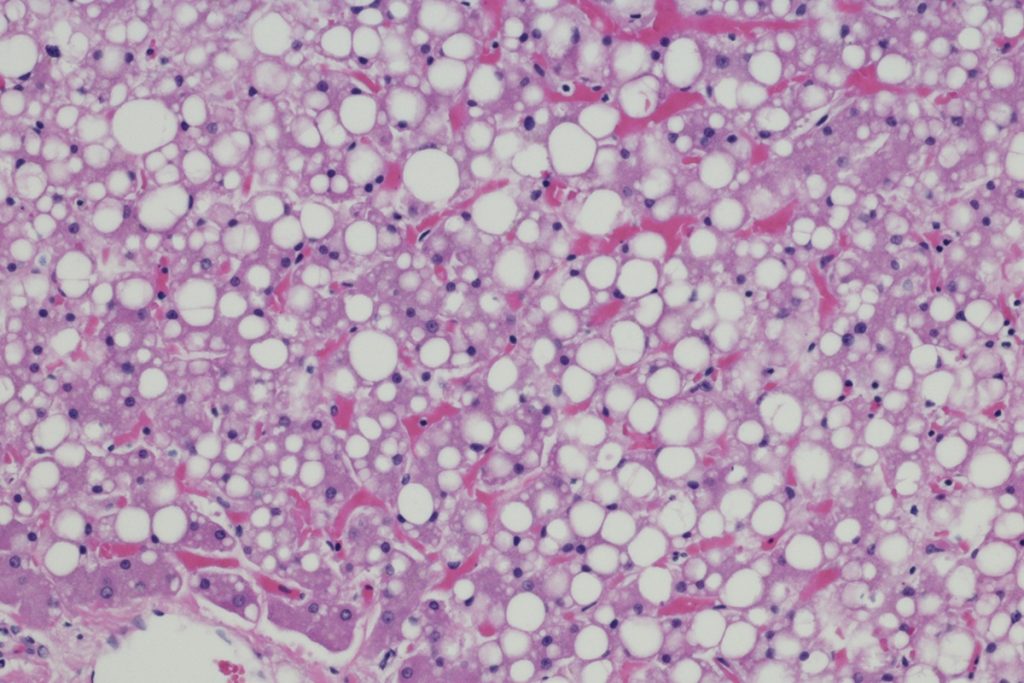

A equipe investigava inicialmente a localização correta da proteína e descobriu que ela aparece em gotículas lipídicas e também no núcleo de adipócitos. Nesse ambiente, a HSL interage com outras moléculas e colabora com mecanismos de manutenção do tecido adiposo.

O processo descoberto por eles revela que a adrenalina ativa a HSL e estimula a saída da proteína do núcleo das células de gordura durante períodos de jejum. Em camundongos obesos, há uma concentração no núcleo, como se as proteínas lá presas não pudessem iniciar o processo de queima de gordura.

Os resultados apontam que adipócitos defeituosos resultam tanto em obesidade quanto em lipodistrofia. As duas condições provocam falhas de regulação metabólica e ampliam o risco cardiovascular, mostrando como um quadro aparentemente oposto de saúde pode compartilhar tanto origem como riscos.